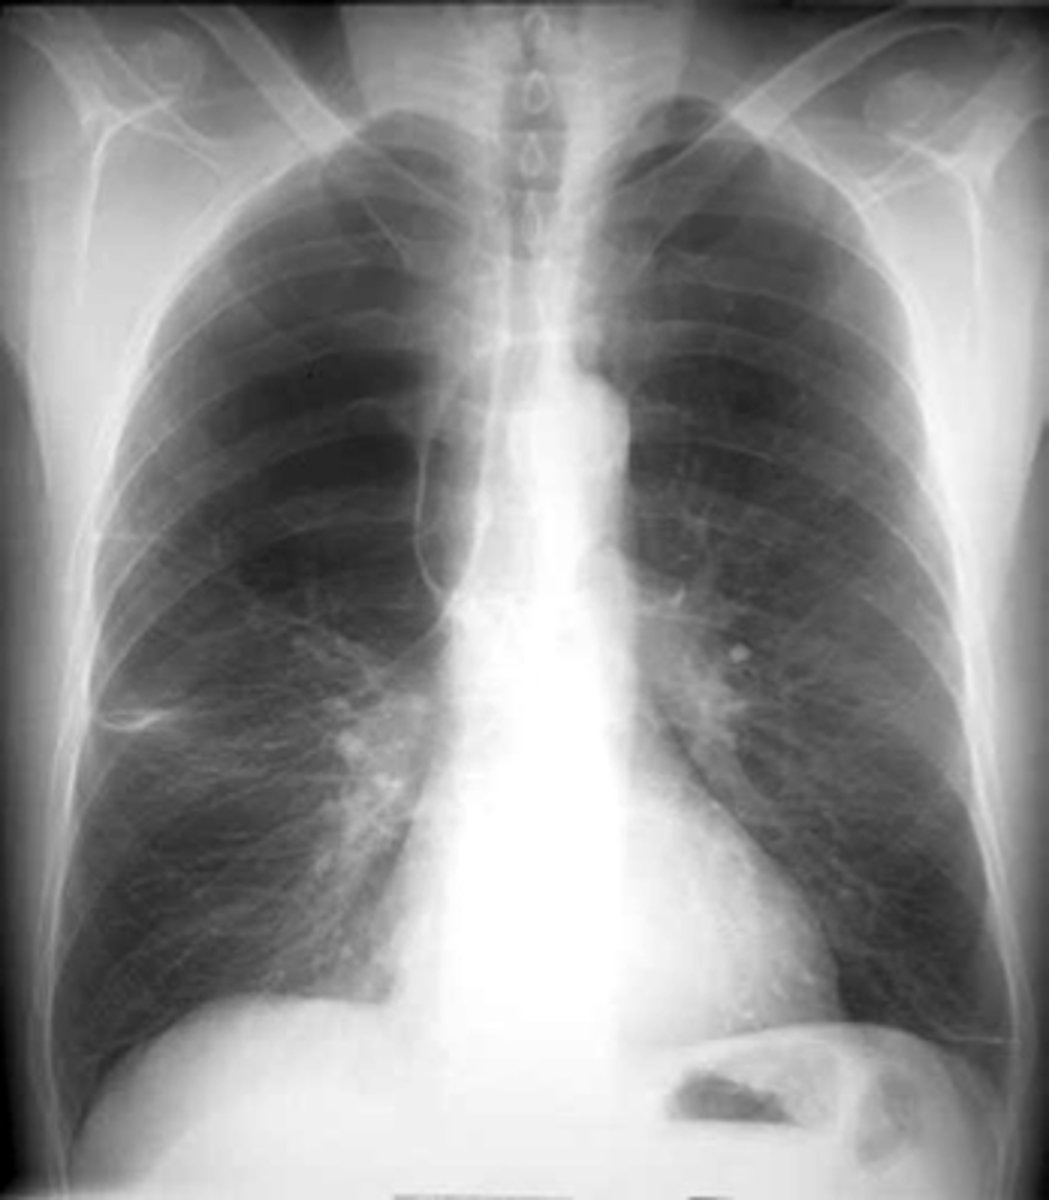

Pleural effusion

knowt flashcard image

Pleural effusion (right sided)